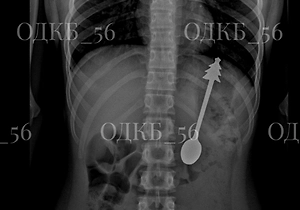

Ранее Life.ru писал о другом необычном медицинском случае в Новосибирске: 17-летний юноша годами жил с почкой, увеличившейся до размеров пятилитровой бутылки. Патологию выявили случайно во время медосмотра перед трудоустройством. У подростка диагностировали выраженный гидронефроз — заболевание, при котором в почке накапливается жидкость и орган значительно увеличивается в размерах.